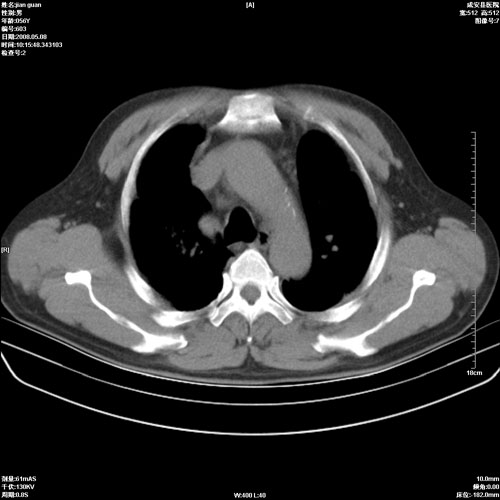

病人 男 60岁 主诉 胸闷 无明显发热 一般情况尚可。

考虑1心功不全,肺水肿

2右上肺结核纤维性病灶、肺气肿

1.右上肺陈旧性肺结核.

2.心脏增大(以左心室增大为著),请结合b超及听诊.

1.两上肺陈旧性结核;慢支肺气肿。

2.肺门血管扩张,心脏增大,为肺心病

考虑.两上肺陈旧性结核;慢支肺气肿。肺心病

1.陈旧肺结核;

2.慢支肺气肿;

3.肺心病.

陈旧性肺结核,左心房扩大,左心衰竭

2右上肺结核纤维性病灶、肺气肿 ,肺心病